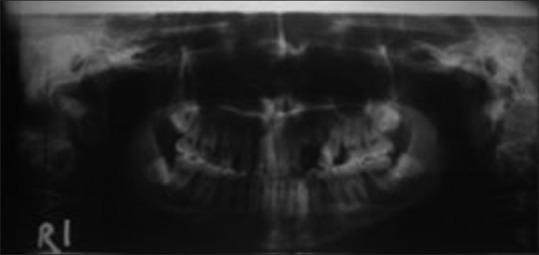

Unilateral condylar hyperplasia is an uncommon condition with unknown etiology which causes overdevelopment of condyle leading to facial asymmetry, mandibular deviation, malocclusion, and articulation dysfunction. Two Indian families with unilateral condylar hyperplasia are presented where the similar abnormality was also detected in one of their parents. The condylar hyperplasia in these two families indicates that mandibular condylar hyperplasia could be genetic in origin.

单侧髁突增生是一种病因不明的罕见病症,它会导致髁突过度发育,进而引起面部不对称、下颌偏斜、错牙合畸形及关节功能障碍。本文报告了两个患有单侧髁突增生的印度家族,在他们的一位家长中也检测到了类似异常。这两个家族中的髁突增生表明下颌髁突增生可能起源于遗传。